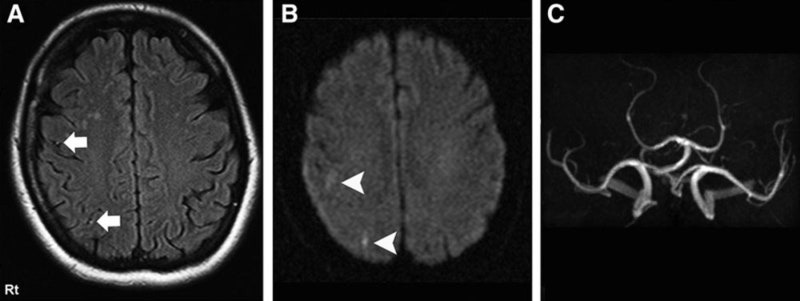

- ๋ณ์์ ๋์ฐฉํ๋ฉด CT ๋๋ MRI ๊ฒ์ฌ, ํ๊ด์ดฌ์ ๋ฑ์ด ์ด๋ฃจ์ด์ ธ ์์ธ ๊ท๋ช ๋ฐ ์น๋ฃ๊ณํ์ด ์ธ์์ง๋๋ค. PMC

๋๊ฒฝ์ ์ ์กฐ์ฆ์์ด ์์ฌ๋ ๋๋ MRI๋ CT ๊ฒ์ฌ๋ก ํ๊ด ์ํ๋ฅผ ์ ํํ ํ์ธํ๋ ๊ฒ์ด ์ค์ํฉ๋๋ค.

MRI๋ ํ๋ฅ ์ฐจ๋จ ๋ถ์๋ฅผ ์ธ๋ฐํ ๋ณผ ์ ์๊ณ , CT๋ ์ถํ ์ฌ๋ถ๋ฅผ ๋น ๋ฅด๊ฒ ํ์

ํ ์ ์์ต๋๋ค.